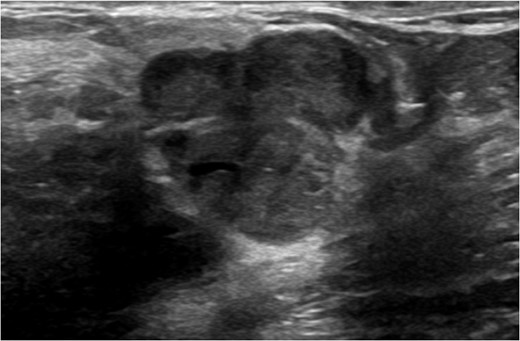

A 56-year-old black female presented to the surgical clinic with a palpable left breast mass that had grown over several months. She denied nipple discharge, breast retraction or family history of malignancy. Physical exam revealed a palpable, subareolar mass without skin changes or asymmetry, and no lymphadenopathy. Her mammogram revealed a 5.4 × 3 cm lesion behind the nipple with Breast Imaging-Reporting and Data System (BI-RADS) 5 classification. An ultrasound indicated a 2.2 × 2 cm lobulated hypoechoic mass with BI-RADS 4 classification (Figs 1–3).

Ultrasound of left breast showing multilobulated lesion BI-RADS 4.